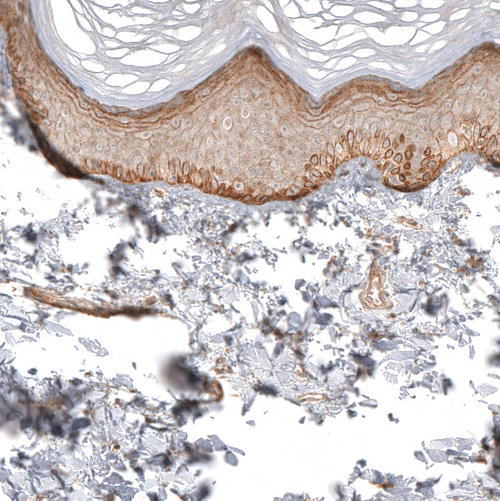

Immunohistochemical staining of human prostate shows moderate membranous and cytoplasmic positivity in smooth muscle cells and glandular cells.